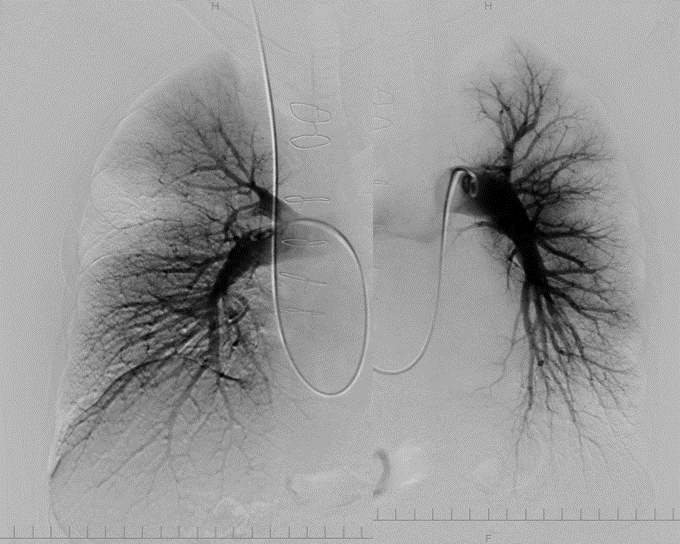

・肺動脈造影検査:【術前】矢印:主な狭窄や閉塞病変部位

【術後】矢印部分の血流改善を認める